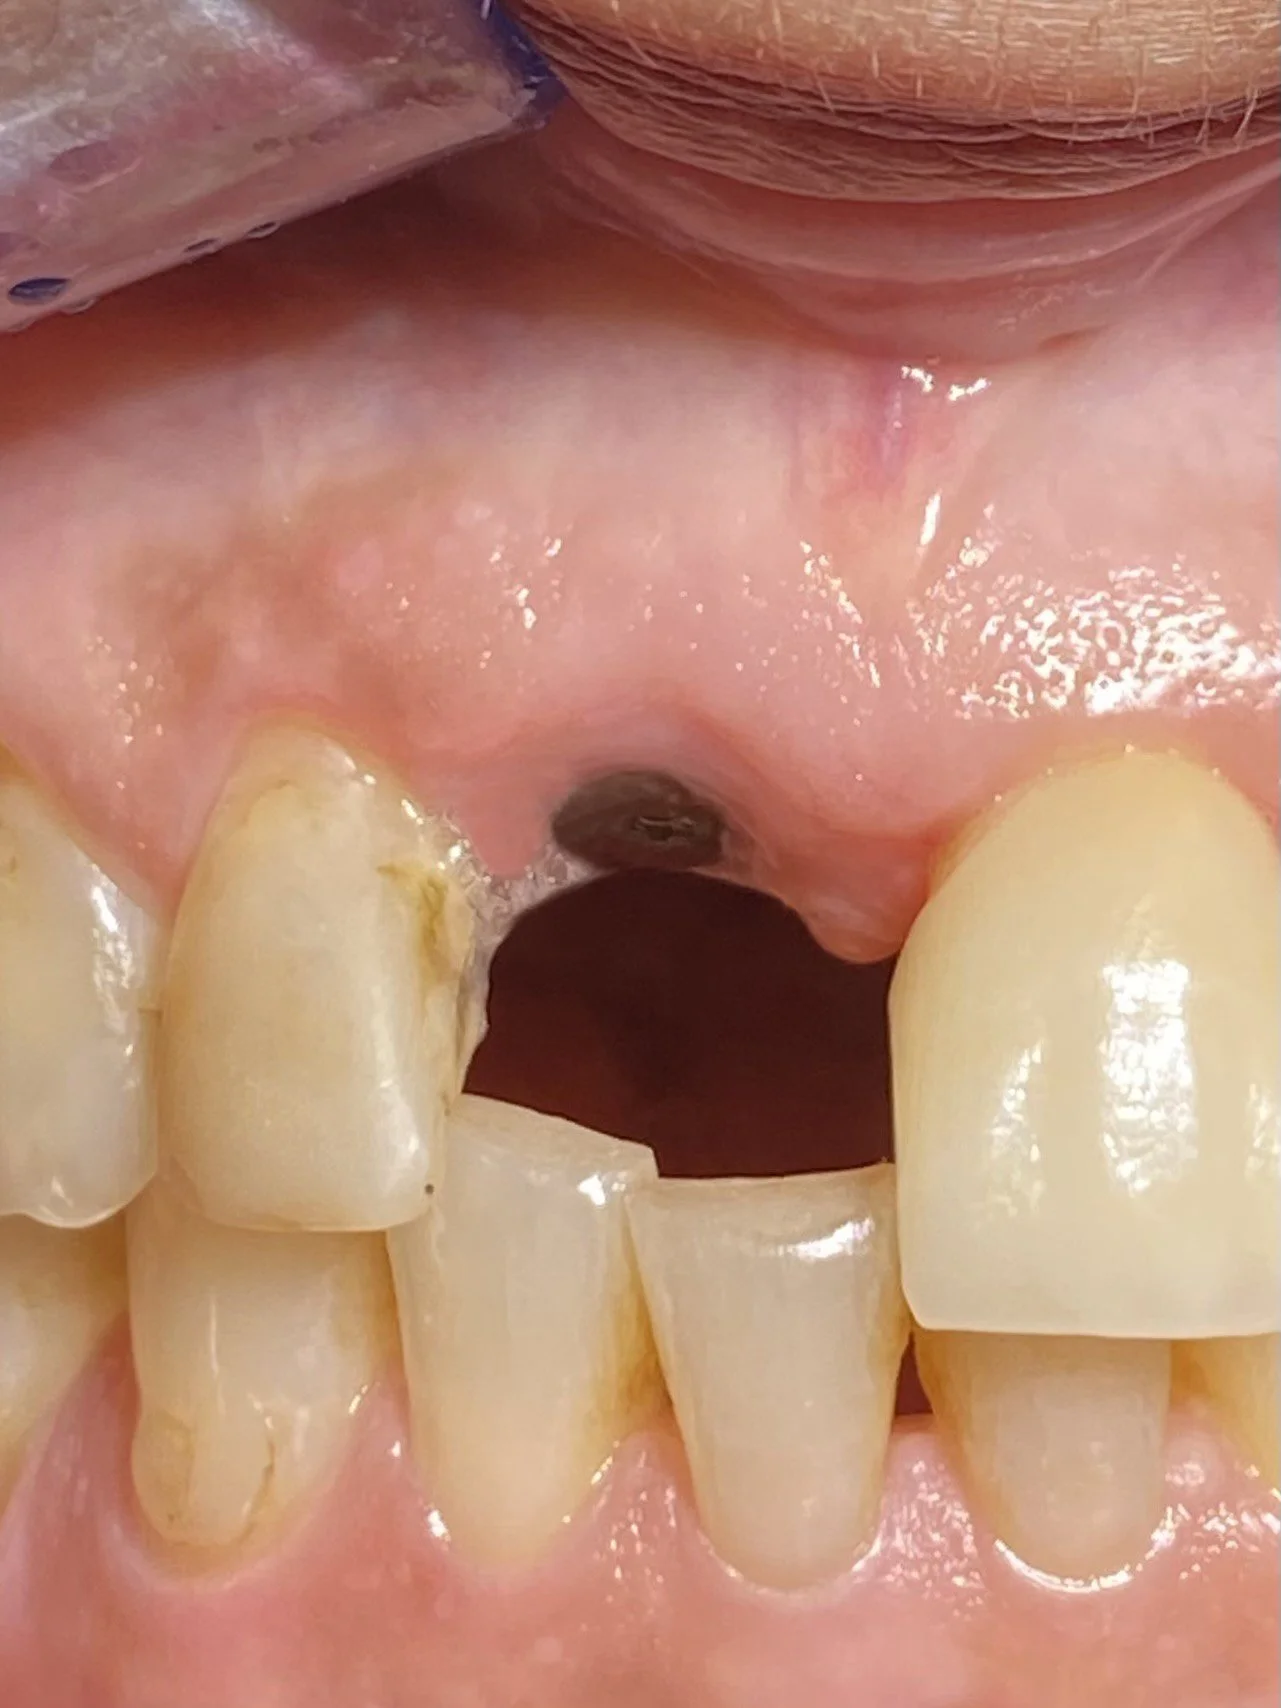

The patient was referred to me in 2021 at Lismore and I referred the patient to a Periodontist in Brisbane. He extracted the tooth, placed a temporary partial denture plate to fill the space and subsequently placed a Straumann implant fixture and healing cap

-

I completed this case at Lismore in 2022 and this radiograph illustrates the completed the screw accessible zirconia implant crown